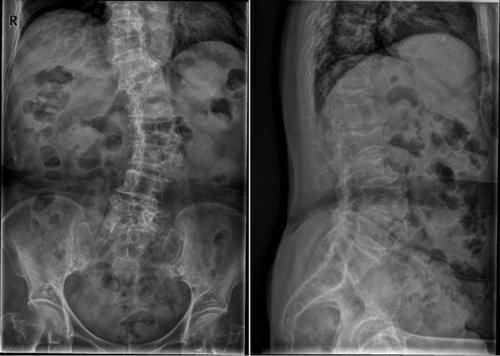

Case19:M,49y;左侧腰背部疼痛1天。

文章插图

Case20:F,78y;胸背痛2周。

Case21:M,49y;肾癌病史。